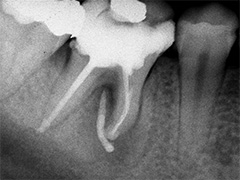

Dieser Zahn wurde schon geraume Zeit zuvor von einer Kollegin im Notdienst eröffnet und anschlies­send mit einer aufwendigen Amal­gamrestauration ästhetisch an­sprechend wieder verschlossen. (Bild 1) Uns blieb noch WK/WF, was bei massiver Überstopfung der hin­teren Wurzel auch gelang (Bild 2).

"Überstopfen ist immer noch besser als Unterstopfen" laut Koçkapan. OK, hier wurde des Guten aber ganz eindeutig zuviel getan.

Also direkt neben dem Zahn das Zahnfleisch ein wenig angehoben und zur Seite gedrängt und dann mit einem scharfen Löffel den Überschuss vollständig entfernt.

Schon 8 Monate später ist eine deutliche Verbesserung der Gesamt­situation unverkennbar (Bild 3). Verlorengegangene Knochensubstanz wurde in Teilen schon wieder aufge­baut, doch ist noch gar nichts entschieden. Schaun mer also ma'.

Abrechnungstechnisch hat der Mut zur WR an 38 gefehlt, deshalb nur EXZ1.